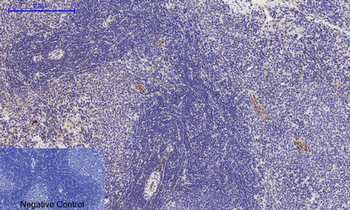

Immunohistochemical analysis of paraffin embedded Human astroglioma tissue labeling Tau with orb1294394 at 1/300.